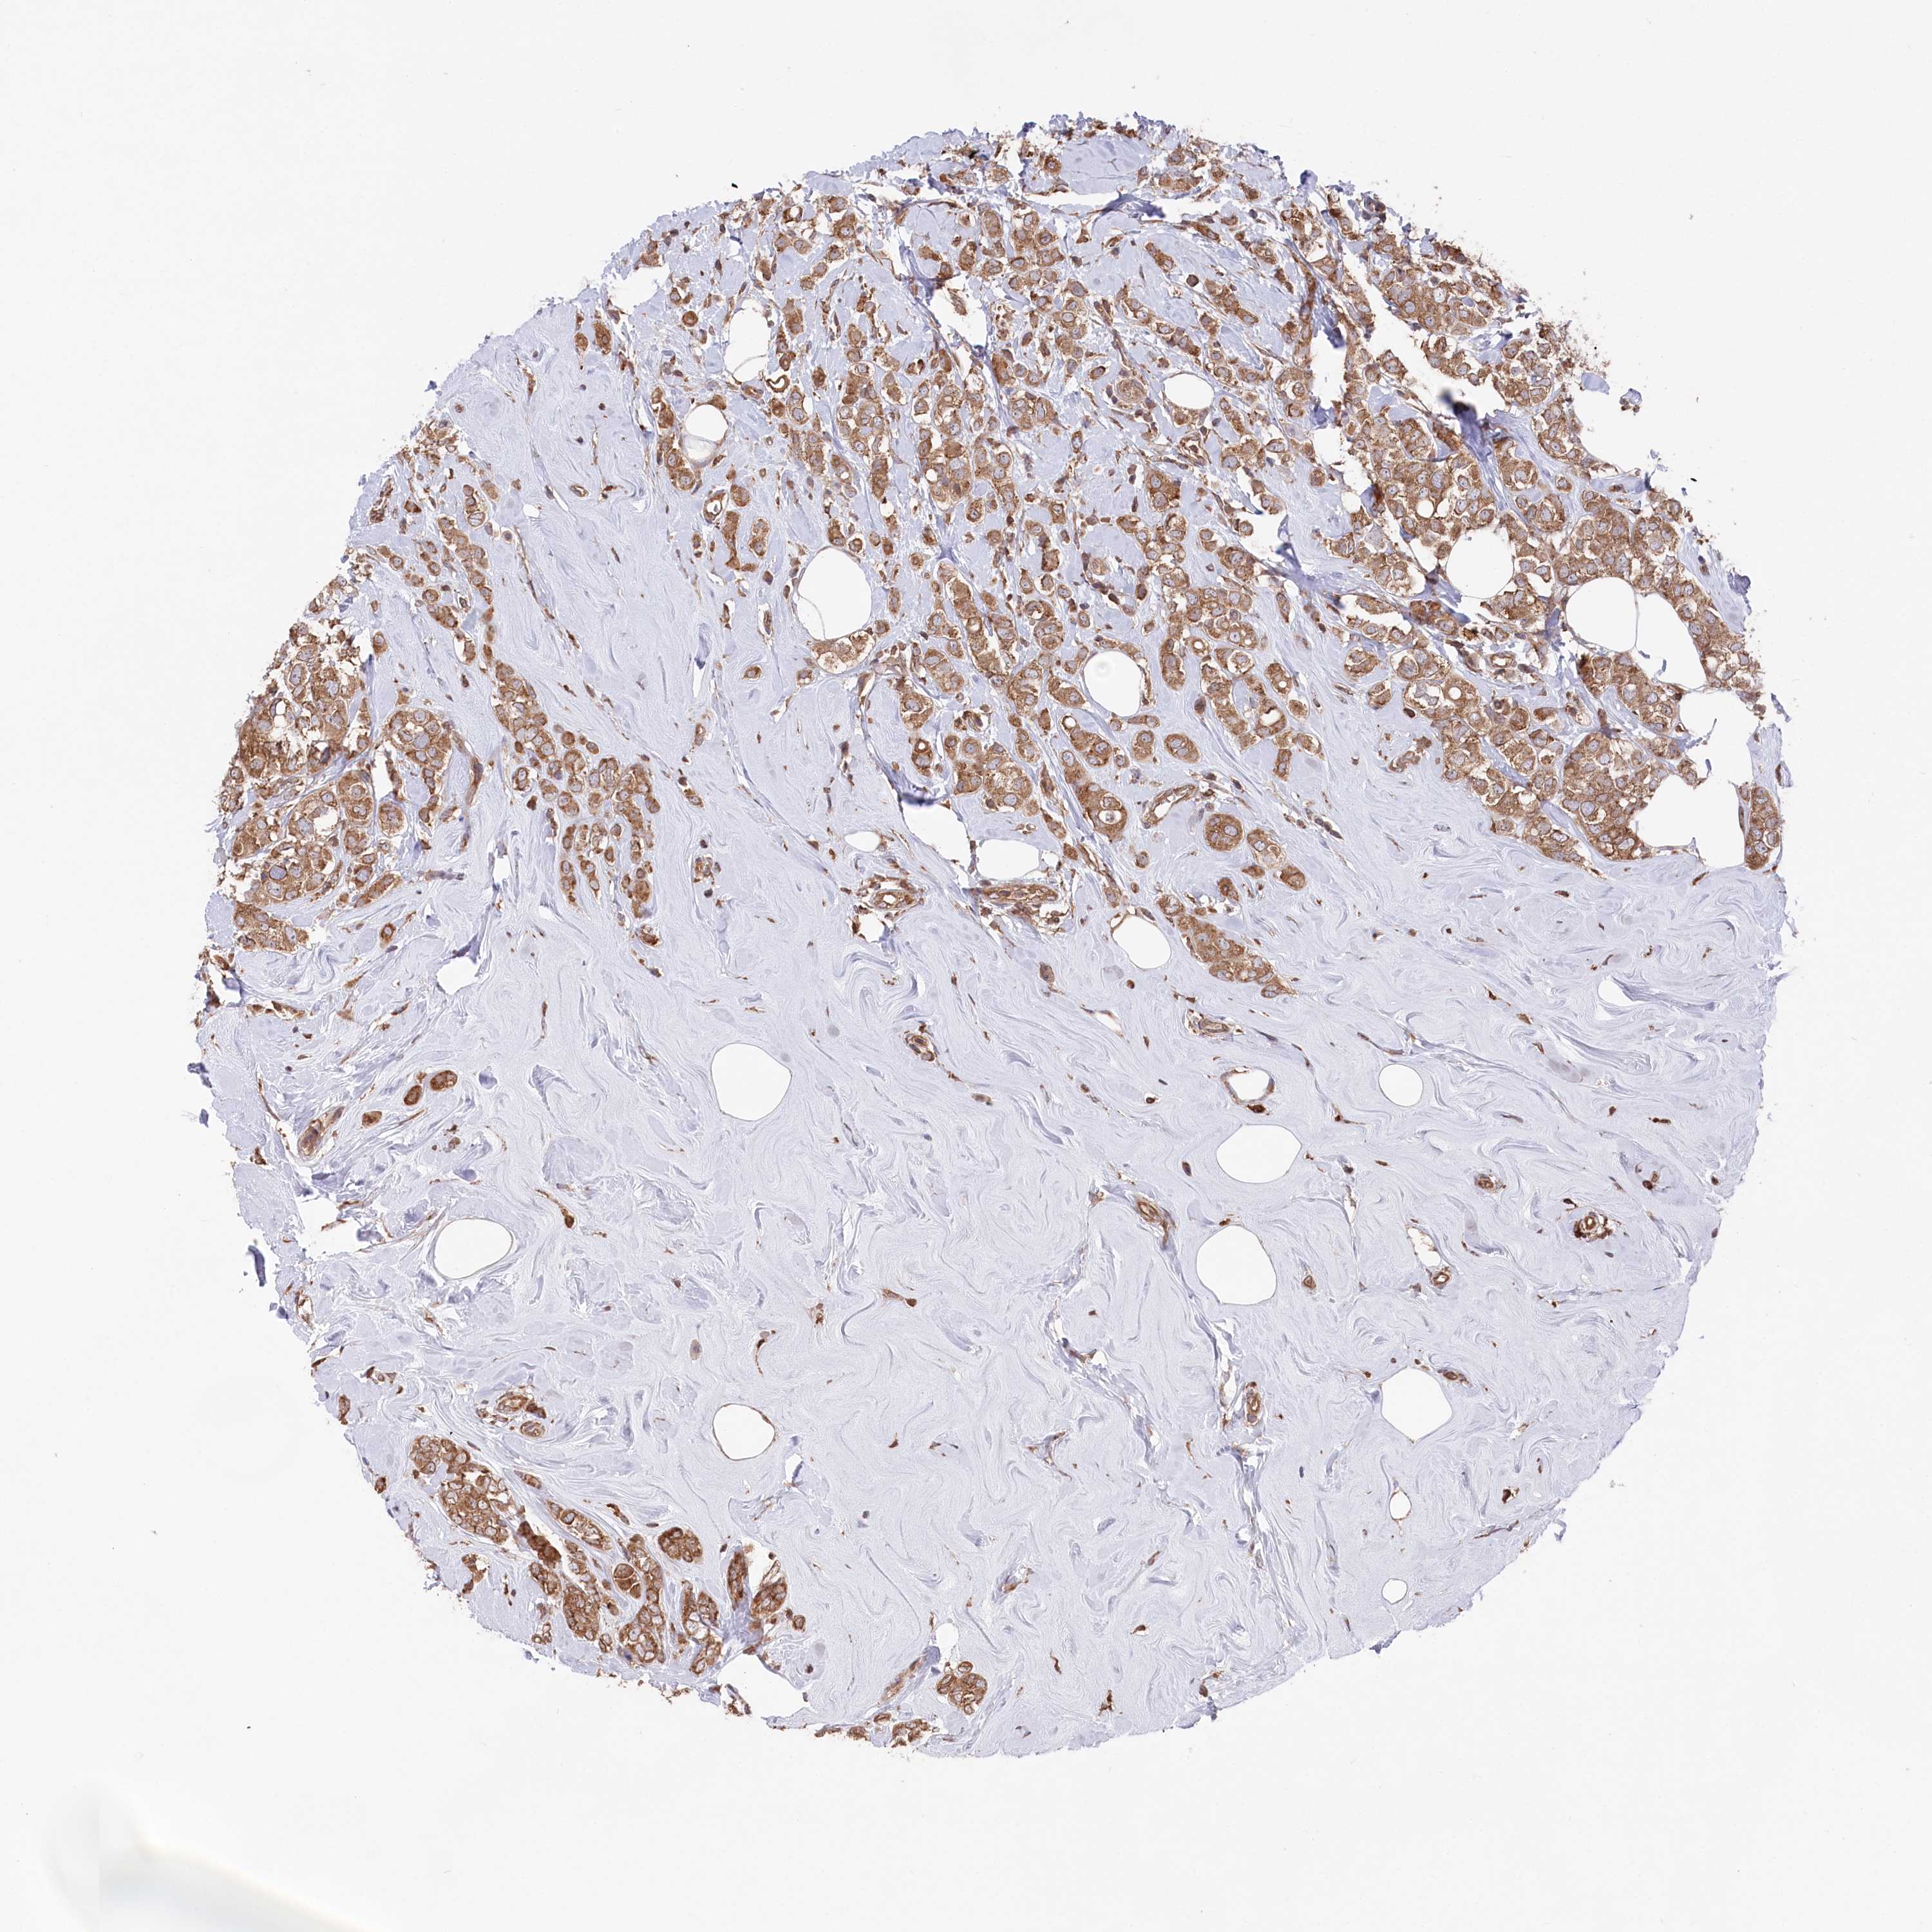

CANCER BREAST CANCER Show tissue menu

BRCA TCGA BRCA VALIDATION PROTEIN EXPRESSION

ANTIBODIES

AND

VALIDATION